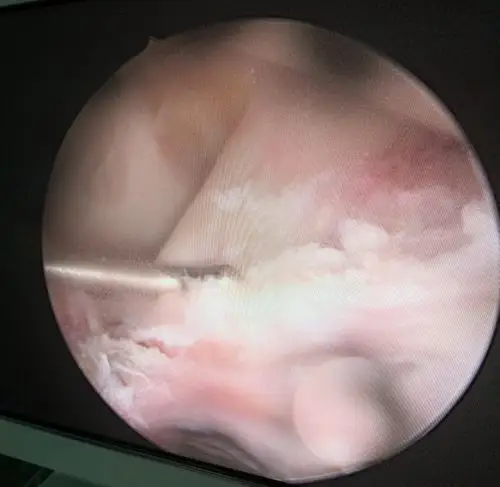

胫骨髁间棘撕脱骨折关节镜下固定一例